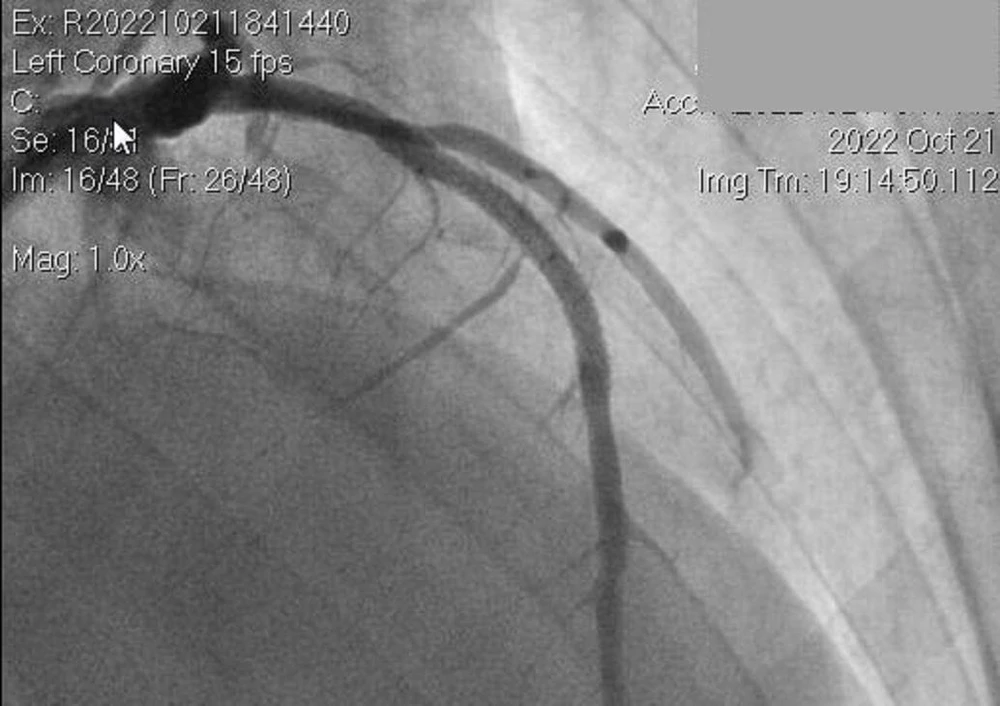

Hình ảnh chụp mạch máu của bệnh nhân THT. Ảnh: BVCC |

Sau khi tiếp nhận, êkíp trực cấp cứu của BV Nguyễn Tri Phương hội chẩn với BS chuyên khoa tim mạch can thiệp, chẩn đoán đây là trường hợp nhồi máu cơ tim cấp thành trước rộng giờ đầu, biến chứng ngưng tim ngoại viện đã được hồi sức thành công. Chỉ định phải tái thông mạch vành cấp cứu.

Sau 30 phút can thiệp, bệnh nhân đã được thông tắc một nhánh động mạch vành lớn nhất, sau đó chuyển về khoa tim mạch can thiệp theo dõi và điều trị tiếp.